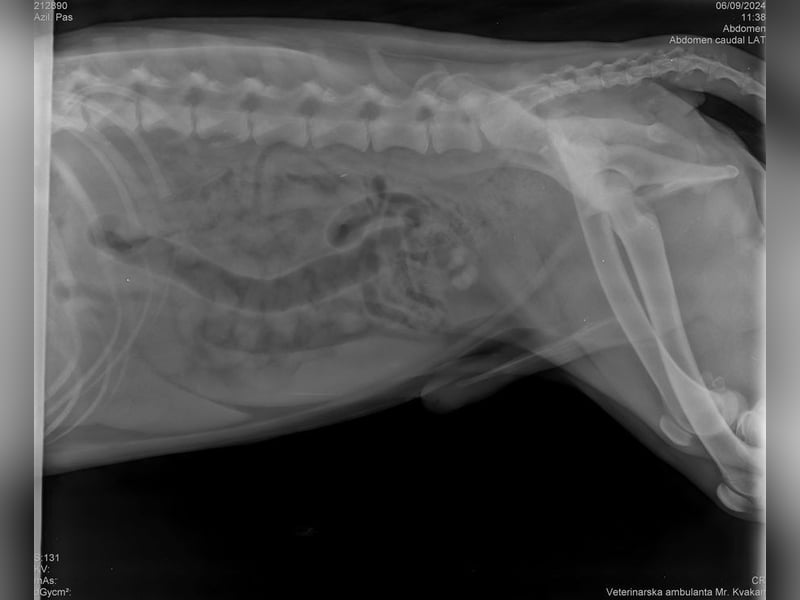

Bemerkungen: Ein Hinterbein ist etwas kürzer

Wir durften ihn deshalb ohne Probleme mit ins Tierheim nehmen, da Yondu Probleme mit der Hüfte und ein etwas kürzeres Beinchen hat. Youdu hat bei einen Besuch beim Tierarzt entsprechende Röntgenbilder von Hüfte und Hinterbeinchen, die den Interessierten in der Bildergalerie zur Verfügung gestellt werden.